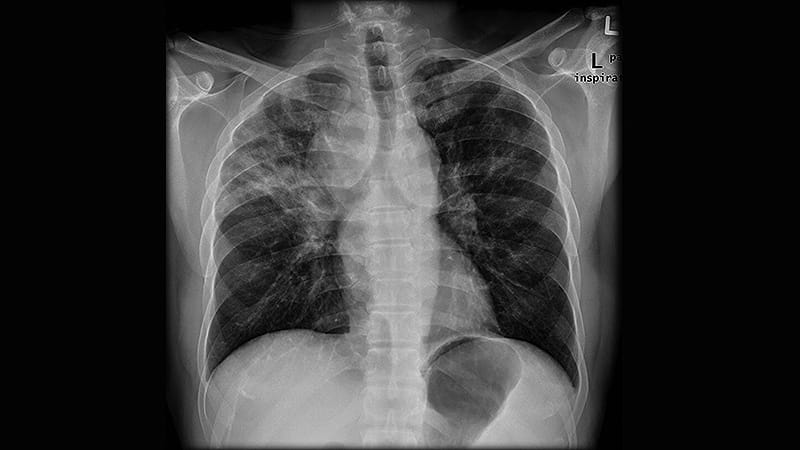

Lung Disease Raises Mortality Risk in Older RA Patients -